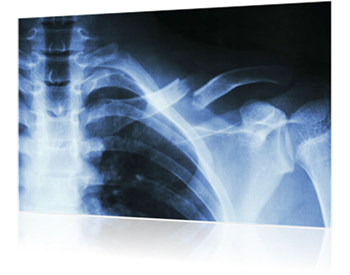

Bones are fragile. It is no surprise then, that the powerful impact of an automobile collision often results in broken bone injuries. Any bone is vulnerable in an accident, but the following are the bones that generally tend to break in car wrecks:

• Skull

• Collarbone

• Ribs